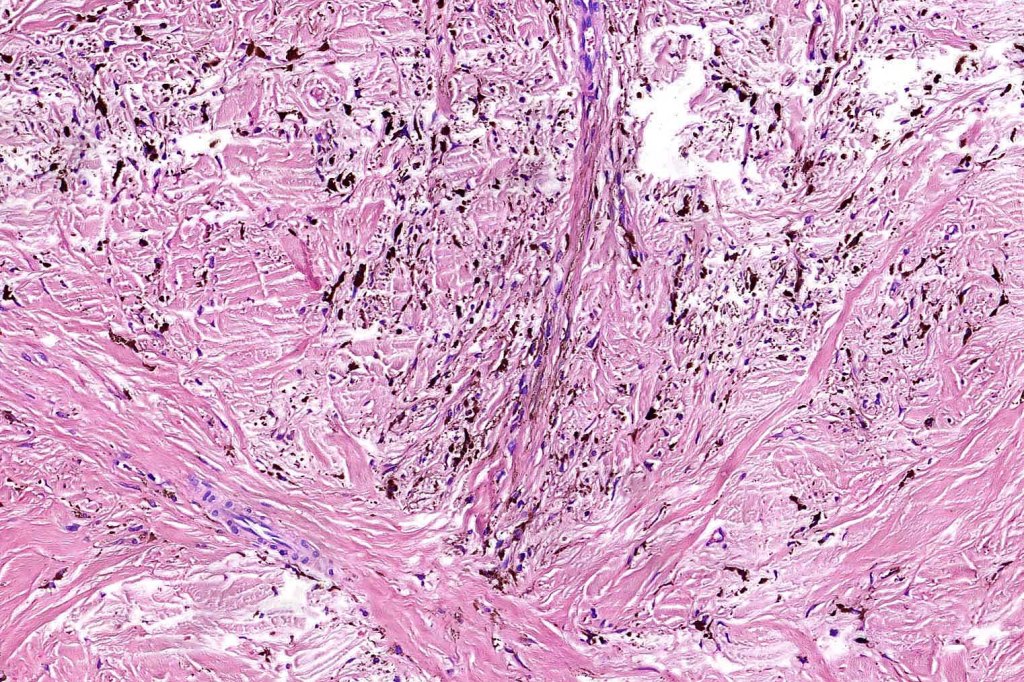

Histologically, it is characterized by a dense population of spindled, dendritic melnanocytes & melanophages with variable fibrosis. It may sometimes represent a component of a combined nevus. Mitotic activity is not usually present and pleomorphism is absent (see atypical blue nevus below). Involvement of the arrector pili muscle is not uncommon.

•Admixture of spindle cells, pigmented bipolar or dendritic cells & melanophages

•Stromal fibrosis, myxoid change, vascular hyalinization with cyst formation are often seen

•Some tumors are composed spindle cells in a fascicular or neuronevoid pattern